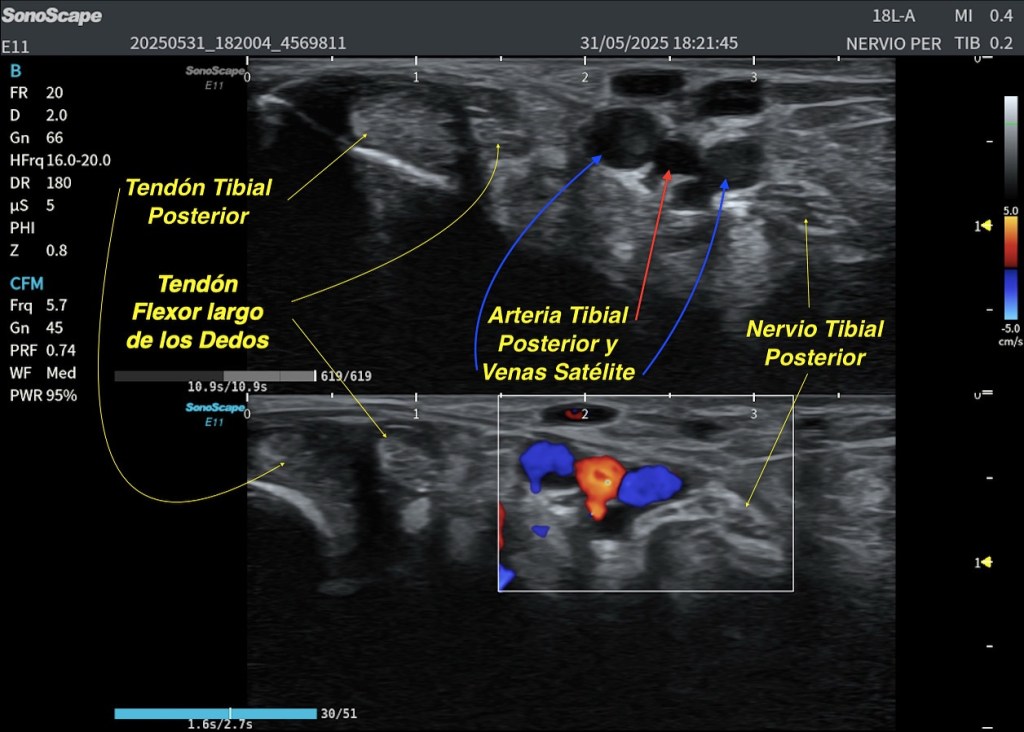

El estudio ecográfico longitudinal y transversal del compartimento posterior superficial muestra:

- Conservación de la continuidad distal con el tendón de Aquiles.